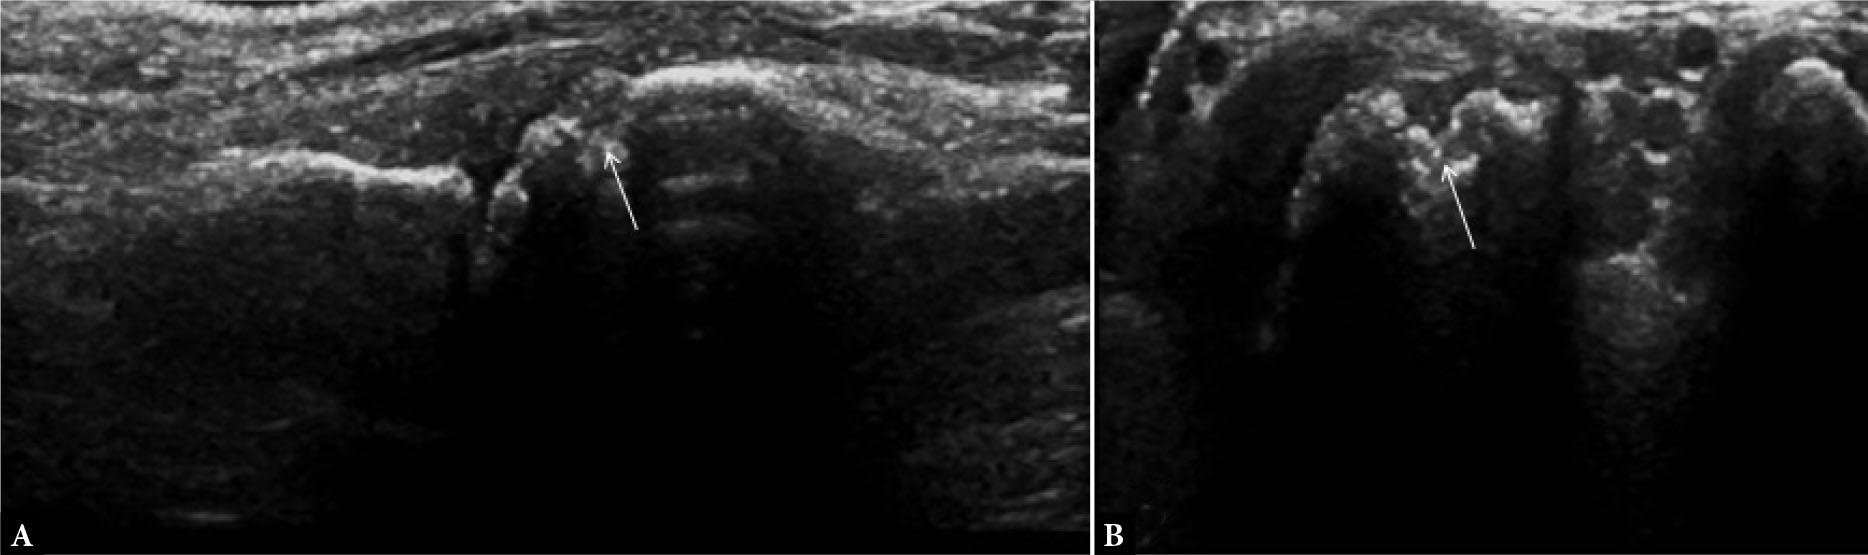

In pseudogout, calcium pyrophosphate crystals deposit (CPPD) as echogenic foci of different sizes or as a linear band within the substance of the hyaline cartilage. These findings have a moderate sensitivity but an excellent specificity to differentiate between gout and pseudogout.

In CPPD disease, echogenic spots may be seen at the fibrocartilage sites, such as the menisci, and triangular fibrocartilage. In the tendons, crystals can appear as linear hyperechoic areas and in the synovial cavity as hyperechoic dots of variable sizes (Fig. 29).

Fig. 29.

Calcium pyrophosphate crystals deposit (CPPD) disease: long-axis US image of medial wrist joint shows nodular hyperechoic deposit in the region of triangular fibrocartilage (arrow in A) which is seen as a calcific opacity in radiograph (arrow in B)